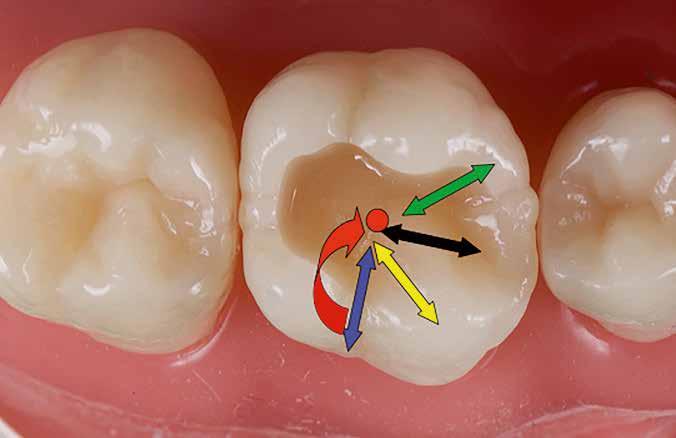

Posselt az állkapocs funkcionális mozgásait a mandibula határmozgásainak görbéjével (Posselt-féle diagram) írta le, amely három térbeli síkra bontható (1. ábra): sagittális, frontális és horizontális. Ebből következik, hogy a fogak dinamikus kölcsönhatása is három dimenzióban értelmezhető [7].

Az egyes csücskök háromdimenzóban végzett, funkcionális mozgáspályáinak összességét nevezzük okkluzális iránytűnek (2. ábra). Az okkluzális iránytű minden csücsök esetében egyedi (a rajta lévő bemélyedések és kiemelkedések szempontjából), és azt a csücsöknek a mandibula condylusának forgásközéppontjához viszonyított helyzete határozza meg.

Az okkluzális iránytű leírásához használt terminológia a The Glossary of Occlusal Terms-ből származik, amelyet a The Glossary Committee of The International Academy of Gnathology állított össze [8]. Fontos megjegyezni, hogy a mandibula mozgásai rágás és nyelés során mindig a maximális interkuszpidációs helyzetből indulnak ki, és oda is térnek vissza.

Ezek a mozgások a következők:

• PROTRUSIO (fekete) – az állkapocs előrefelé irányuló mozgása;

• LATEROTRUSIO (kék) – oldalirányú vagy kifelé történő mozgás;

• LATEROPROTRUSIO (sárga) – kifelé és előre irányuló mozgás kombinációja;

• LATERORESURTRUSIO (piros) – kifelé, hátrafelé és felfelé irányuló mozgás. Ez a mozgás Bennett-mozgásként ismert, Norman G. Bennett (1870–1947) után elnevezve;

• MEDIOTRUSIO (zöld) – mesiális oldalirányú, befelé történő mozgás, amely lehetővé teszi az ellenkező oldali condylus lefelé/előre irányuló mozgását [9].

Az iránytű középpontja (az IKP-ben létrejövő érintkezés) körül található egy kisebb szabad zóna, amely lehetővé teszi az antagonista csücsök mozgását a „hosszú centrikus” (Long Centric vagy Freedom in Centric) tartományban [10]. Ez képezi a Polz-féle biomechanikai wax-up [11] alapját, amelyre a DeVreugd-féle okkluzális iránytű is épül. Jelen publikáció célja egy dinamikus alapú, ésszerű megközelítés bemutatása a hátsó fogak direkt kompozittal történő restaurálásához, amelynek eredményeként a rétegezést követően csupán minimális utólagos korrekcióra van szükség. A szerző a rövidebb, lényegre törő bemutatás kedvéért a felső első molárisra fókuszál. Ezt a fogat azért választotta, mert rágás közben ez viseli a legnagyobb erőbehatást, és ezen a fogon található a legtöbb okklúziós érintkezési pont [9].

DeVreugd-féle okkluzális iránytű.